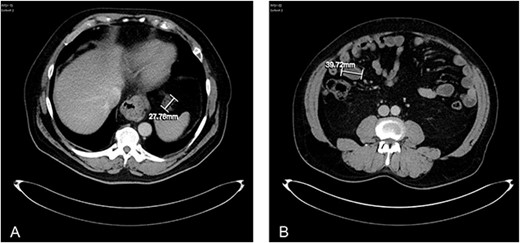

Unfortunately, 2 years later the patient was repeatedly admitted acutely to hospital with vomiting and physical deterioration. CT scans revealed a cystic mass surrounding the jejunal loops and re-appearances of peritoneal deposits, in keeping with aggressive progression of PMP (Fig. 4). The peritoneal multi-disciplinary team agreed not to go ahead with cytoreductive surgery and HIPEC.

(A) axial CT abdomen demonstrating a serosal deposit measuring 27.76 mm. (B) Axial CT abdomen demonstrating a peritoneal abdominal wall deposit measuring 39.72 mm.